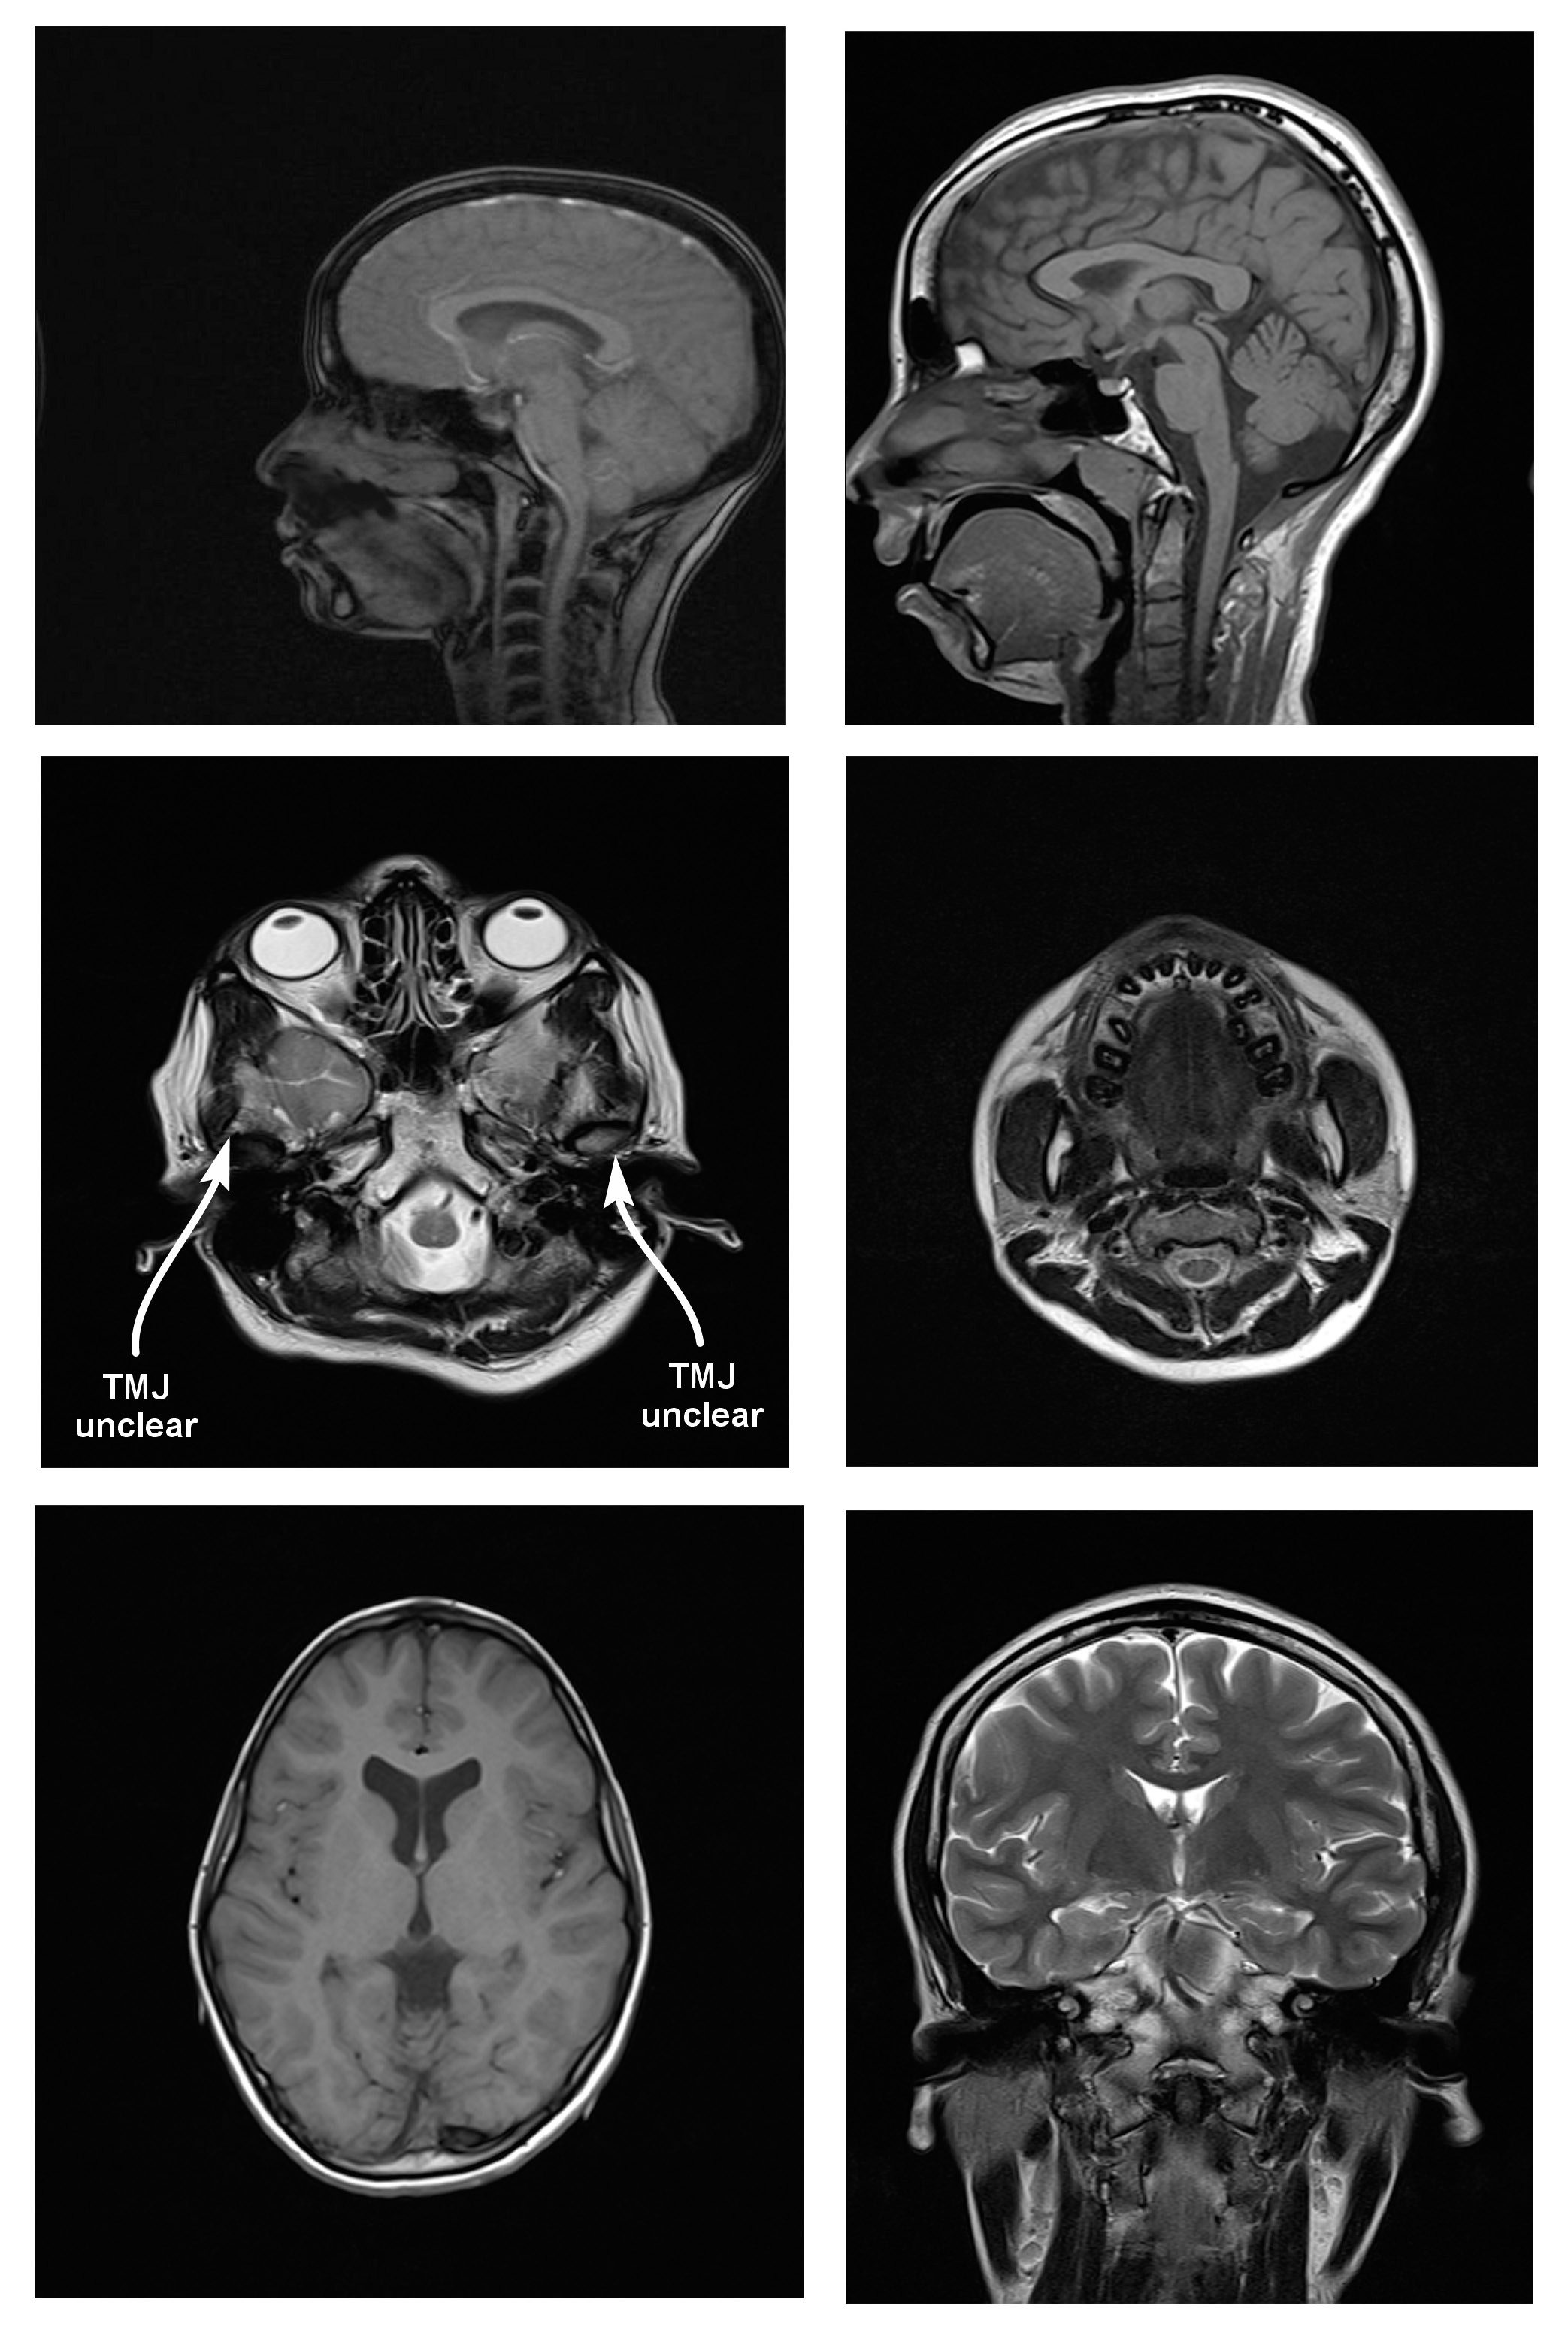

Magnetic resonance imaging scans were taken for all 38 subjects to study diagnostic image quality. Since the orthodontic appliances were securely bonded with orthodontic composite, there were no special precautions taken regarding the possible dislodgement and heating of the appliances, as previous studies had found changes in the temperature of the appliances to be clinically insignificant (within 1°C).16 The MRI scans for all types of bracket and retainer materials are shown in Figure 1, Figure 2, Figure 3, Figure 4, Figure 5, Figure 6, Figure 7, Figure 8, Figure 9, Figure 10. Non-diagnostic or unclear ROI are marked with arrows. None of the patients reported any discomfort or pain during MRI examination. The MRI scans were analyzed by a panel of 6 qualified and licensed radiologists, who assessed their diagnostic quality. The scans were compared with controls that included images from the archives of the Department of Radio-Diagnosis of Kamineni Institute of Medical Sciences. The radiologists ranked the images according to the distortion observed in the abovementioned ROI, using the modified receiver operating characteristic (ROC) analysis of distortion scoring system (Table 2), as described by Elison et al.17 In this method of distortion classification, a score of 3 represents the cut-off point for clinical usability. Images with a score of 3 have moderate distortion or artifacts, but they can still be used for diagnosis.

In the present study, stainless steel buccal/labial and lingual orthodontic brackets caused more distortion of cranial MR images and received higher distortion scores for all anatomic sites than other orthodontic bracket and retainer materials. The mean distortion score assigned by the radiologists to stainless steel appliances was 3.67. According to the anatomic landmarks, it was 4 by the same radiologists for TMJ, the tongue, the maxilla, the mandible, and the maxillary sinus, which means maximum distortion of the MR images. However, it was only 1.16 for the posterior cerebral fossa. This indicates that stainless steel buccal/labial and lingual brackets caused distortion that was most severe in the anatomic sites adjacent to them. The mean score of 1.16 for the posterior cerebral fossa means that there was almost no distortion, which shows a pattern of reduced artifacts with an increasing distance of the anatomic site from the brackets.

Since stainless steel buccal/labial and lingual brackets consistently had higher distortion scores, the MR images were considered non-diagnostic. The results of this study are similar to those obtained by Patel et al.,8 Elison et al.,17 Razdan and Rani,23 Beau et al.,24 Zhylich et al.,25 and Cassetta et al.26 However, they are contradictory to the research done by Sadowsky et al., since an older version of an MRI machine was used in their study.12

Stainless steel retainers in both the maxillary and mandibular arch had a mean distortion score of 2.00. The mean distortion scores at the anatomic sites were 2.16 for TMJ, and 2.00 for the tongue, the maxilla, the mandible, and the maxillary sinus, with only the posterior cerebral fossa having a score of 1.00. This means that there was minimal or no distortion for all ROI. Hence, the MR images with stainless steel retainers in the maxillary and mandibular arches were considered diagnostic.

Titanium retainers in the mandibular arch alone had a mean distortion score of 2.00. The mean distortion scores at the anatomic sites were 2.16 for TMJ, 2.00 for the tongue, the maxilla, the mandible, and the maxillary sinus, and 1.00 for the posterior cerebral fossa, which indicates that there was minimal or no distortion for all ROI. Hence, the MR images with titanium retainers in the mandibular arch alone were considered diagnostic. The results of this study are similar to the findings reported in studies by Shalish et al.,28 Beau et al.24 and Zhylich et al.25